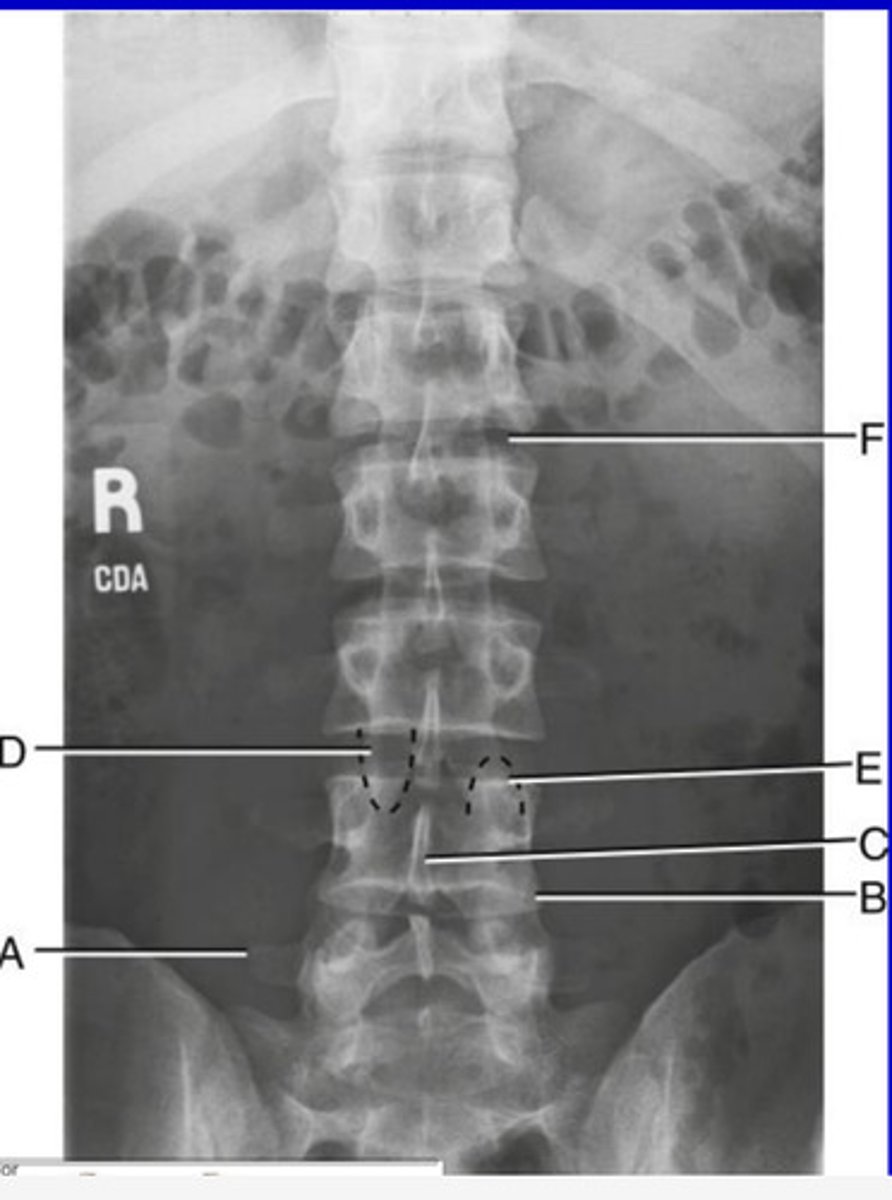

L2 Transverse process

A.

L3 Pedicle

B.

L3 pars interarticularis

C.

L3 inferior articular process

D.

L4 Superior articular process

E.

L3-4 zygapophyseal joint

F.

Oblique lumbar

What position?